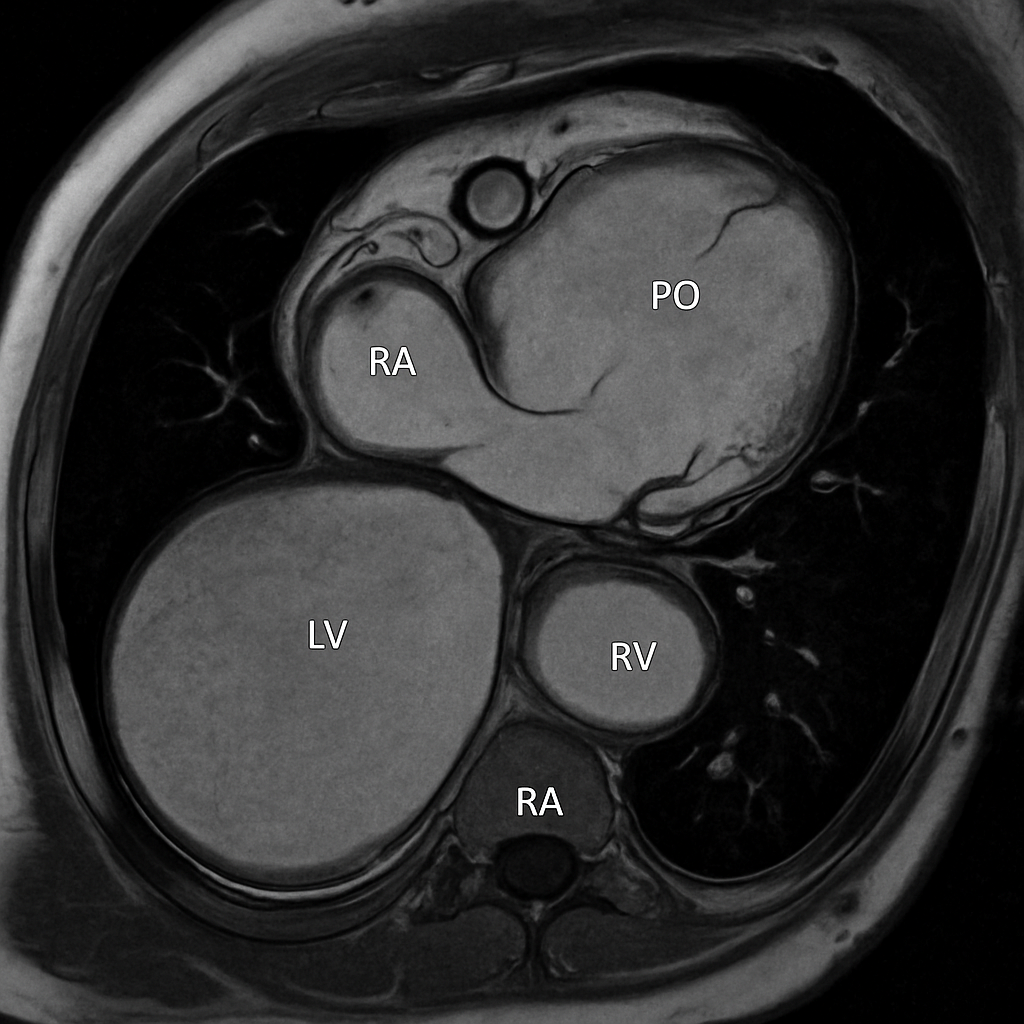

MRI — Short Axis Cine (Systole)

Cardiac MRI short-axis (SA) view at mid-ventricular level during end-systole. SSFP sequence showing thickened myocardium and small LV cavity.

MRI AI Generated 2026-03-16

Ssfp Short Axis Systole

bSSFP cine, mid-ventricular short axis, end-systolic frame. Show concentric LV wall thickening.

OpenAI gpt-image-1